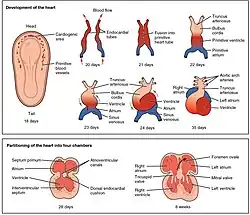

Desenvolvimento

Durante a gravidez, o desenvolvimento do coração tem início com a formação de dois tubos endocardíacos no embrião por volta da terceira semana de gestação. Estes tubos fundem-se, formando um tubo cardíaco primitivo denominado coração tubular.[76] Entre a terceira e quarta semana de gestação, o coração tubular aumenta de comprimento e começa-se a dobrar em forma de "S" no pericárdio, dando ao coração desenvolvido o alinhamento correto. Por volta do mesma altura começam-se a formar os septos e as válvulas e as cavidades começam a tomar forma. Por volta do fim da quinta semana, está concluída a formação dos septos. Na nona semana está concluída a formação das cavidades.[7]

O coração embrionário começa a bater cerca de 22 dias após a fecundação, a um ritmo aproximado do da mãe (75–80 bpm). O ritmo aumenta progressivamente até atingir um máximo de 165–185 bpm por volta da sétima semana de gestação.[77] Após a nona semana, quando se dá o início da fase fetal, o ritmo diminui progressivamente até cerca de 145 (±25) bpm no momento do parto. Antes do nascimento, não existem diferenças de ritmo cardíaco entre os sexos.[78]

Até à quinta semana forma-se no coração fetal um orifício denominado forame oval. Este orifício permite ao sangue passar diretamente da aurícula direita para a aurícula esquerda, desviando-o dos pulmões. Segundos após o parto, este orifício é fechado por uma membrana de tecido denominada septo primário, que até esse momento funcionava como válvula, dando assim início ao padrão de circulação de sangue regular.[7]